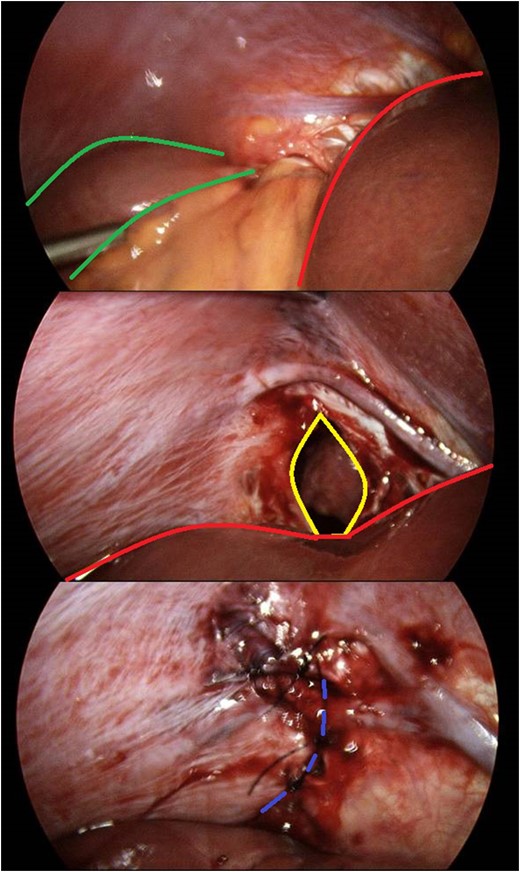

There was evidence of small bowel obstruction, with distended small bowel loops and constriction at the defect. The defect’s location did not appear consistent with a congenital hernia. The hernia was reduced by gentle traction and the defect was closed laparoscopically with interrupted 0-monosof sutures. The entire small bowel was viable and intact (Fig. 3).

Identification and laparoscopic reduction of diaphragmatic hernia in sequence. Green borders outline small bowel; red borders delineates hepatic edge; yellow margins signifies diaphragmatic defect; and purple hashed line is closed defect.